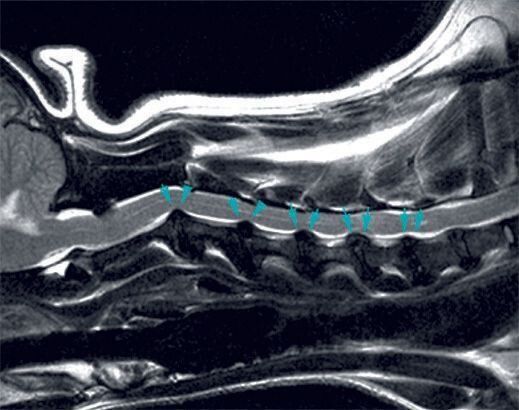

頸部椎間板ヘルニアのMRI画像。複数の椎間板が突出し、神経を圧迫している

犬の背骨は7個の頸椎(けいつい)、13個の胸椎(きょうつい)、7個の腰椎(ようつい)、3個の仙椎(せんつい)の骨から成り立っています。これらの骨の間で、いわば“クッション”の役割を果たしているのが椎間板。その椎間板が正常な位置からずれて、脊髄を圧迫している状態を「椎間板ヘルニア」と呼びます。